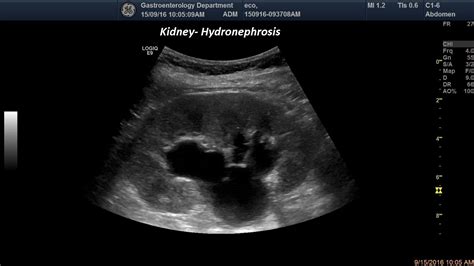

Diagnosing hydronephrosis involves a combination of medical history, physical examination, and diagnostic tests. The goal is to identify the underlying cause of the obstruction and determine the best course of treatment. Common diagnostic tests include:

• Ultrasound: An imaging test that uses sound waves to create pictures of the kidneys and urinary tract.

• hydronephrosis of kidney ultrasound